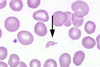

What cell is this?

Eosinophil of a horse